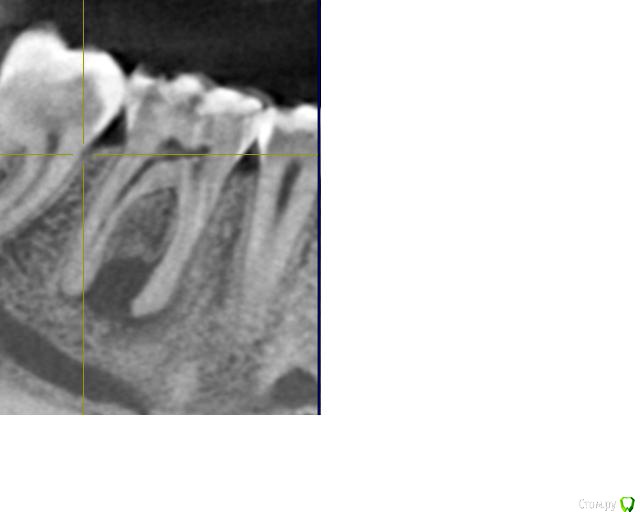

Ксения_ Опубликовано 27 августа, 2015 Поделиться Опубликовано 27 августа, 2015 (изменено) Здравствуйте Уважаемые Доктора! КТ сделано 4 мес назад. После этого пролечен кариес 14, 16, 37, 35. Пролечен пульпит 25, 36.Осталось пролечить пульпит в 15, 26, 47. Удалить все восьмерки.Далее ортодонтия. Стоит вопрос об удалении 46. Зуб ранее был пролечен другим врачом некачественно (+ пропущен канал).Мой лечащий доктор, после консультаций с коллегами, предлагает удаление, т.к. с его слов прогноз у этого зуба неблагоприятный (считает, что через пару лет процесс повторится) и смысла в столь дорогом лечении нет. Мне, конечно, хотелось бы по возможности зуб сохранить.Как вы считаете какой прогноз у этого зуба? P.S. Зуб не беспокоит. Точнее ни один зуб у меня вообще ни разу в жизни не болел (несмотря на такое количество пульпитов, которые для меня были неожиданностью. Врачу своему доверяю.). Несколько докторов которые меня смотрели считают, что у меня высокий болевой порог. Изменено 27 августа, 2015 пользователем Ксения_ Ссылка на комментарий

M@estro Опубликовано 27 августа, 2015 Поделиться Опубликовано 27 августа, 2015 (изменено) Судя по рентгену - прогноз благоприятный. Зуб сохранен,это главное. "процесс повторится" - на это при современном подходе выделяют не более 5 % .Если бы у меня 95 % вероятности в казино было - я бы дом поставил , не то что зуб полечил ) Ключевое при перелечивании - соблюдение современного протокола лечения. P.s. После лечения уже больше двух лет прошло,недавно был на осмотре - процесс все никак не повторится )) Изменено 27 августа, 2015 пользователем M@estro 3 Ссылка на комментарий